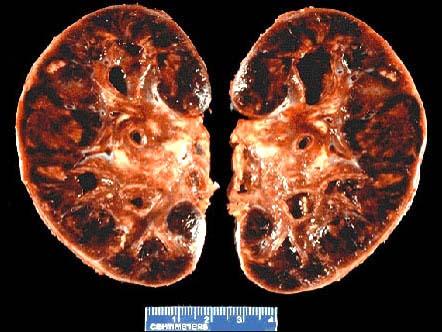

问题 某肾移植患者出现急性排斥反应,其双肾可出现如图所示的改变,关于肾急性排斥反应,下列说法错误的是 ( )

选项 A.经过免疫抑制治疗的患者,该排斥反应在移植后数天内发生 B.细胞型排斥反应镜下可见肾间质明显水肿伴大量细胞浸润,以单核细胞和淋巴细胞为主 C.血管型排斥反应表现为肾细、小动脉的坏死性血管炎 D.血管型排斥反应的肾脏肉眼观见肾明显肿大,呈暗红色并有出血点,可见黄褐色梗死灶 E.急性排斥反应可以细胞免疫为主,也可以体液免疫为主